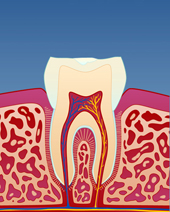

figur III